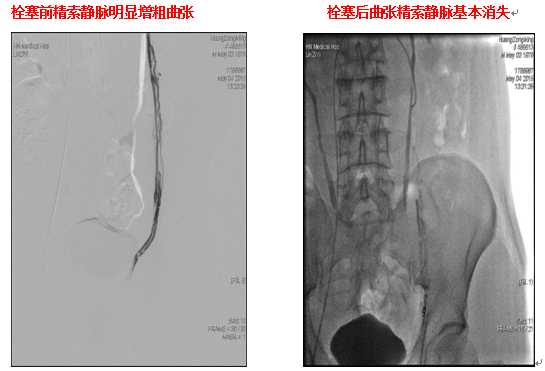

介入微创不开刀也能治疗精索静脉曲张

精索静脉曲张是男性常见的泌尿生殖系统疾病,由于包绕精索的精索静脉扩张常引起血管性精子发生障碍,是导致男性不育的主要原因。患者常常由于缺乏自觉症状而得不到及时诊治,最终导致部分患者生精能力受损。少数患者...